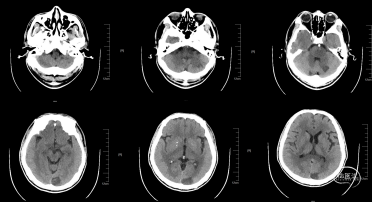

术后即刻CT

术后24小时CT